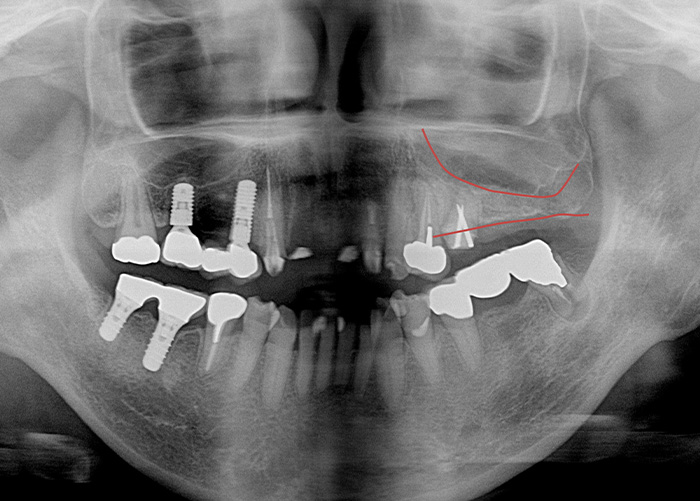

Case.07

![]() |

|---|

| 主訴 | 左上は骨が少なくインプラントできないといわれた。 |

|---|---|

| 治療期間 | 6か月 |

| 治療費 | 50,000円(税込55,000円)(サイナスリフト クレスタルアプローチ・ソケットリフト) |

| 治療内容 | 左上の顎の骨を一部分だけ増やす治療です。 やせ細った顎の骨と、下がってきた上顎洞粘膜との間に人工骨を入れて、骨ができるのを待ちます。 |

| 治療のリスク | 一時的な鼻出血、内出血、眼出血、上顎洞炎、腫脹のリスクがあります。 |